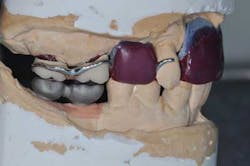

Figs. 6 a, b, c, and d: RPD framework try-in, bite record with mandibular implant-supported metal frameworks and mounting